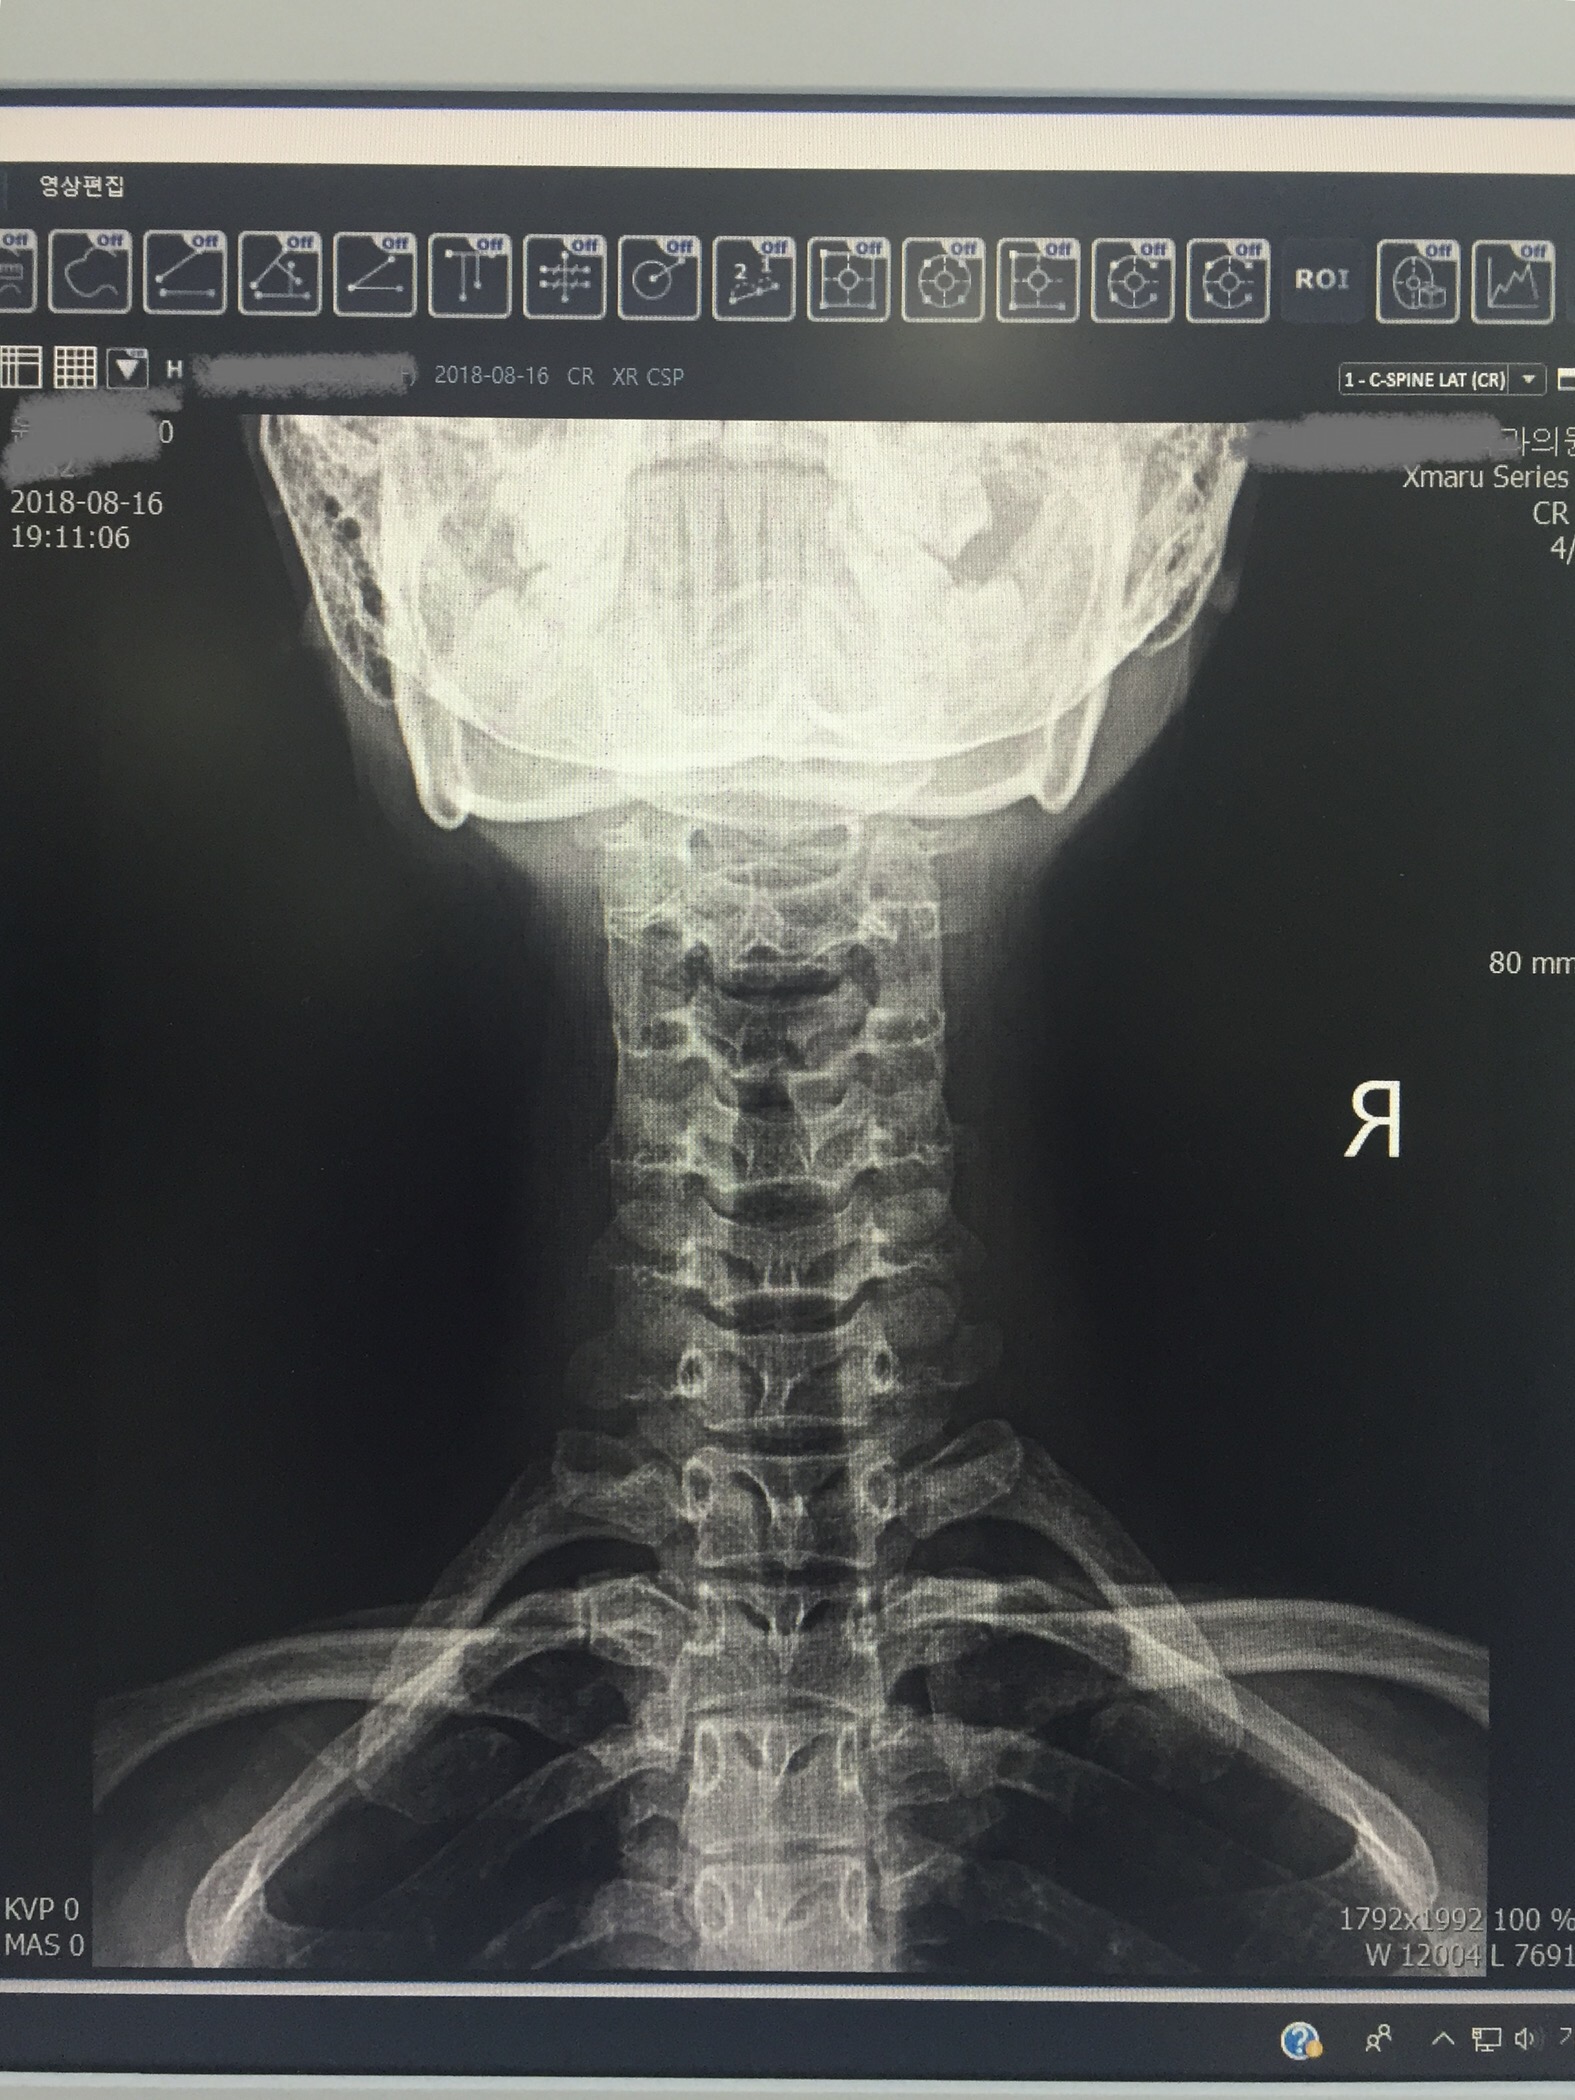

아래 사진은 오늘 찍은것은 아니고, 2년전에 찍은 엑스레이다. (정확하게는 2년 2개월 전)

오늘 찍은 엑스레이는 사진으로 못남겨왔다ㅠㅠ

근데 아래 사진에서 더 나빠졌을줄알고 걱정했는데 그렇지는 않았다. 꾸준히 발레를 해서 주 2회이상 목스트레칭을 의식적으로 해준 덕분이라고 생각하고 있음.